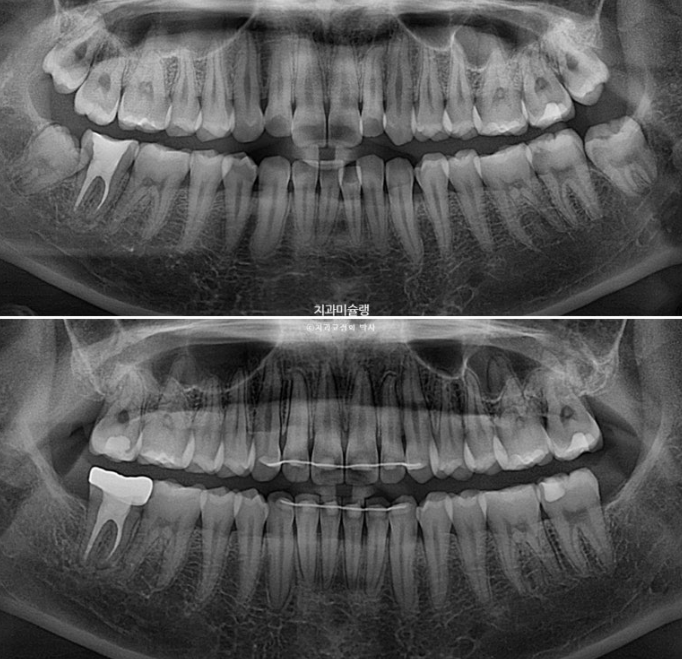

사랑니를 빼고 사랑니 공간으로 어금니를 후방이동 시켜 교합관계를 맞추고 덧니 해소할 공간을 얻기로 합니다.

첫세트 장치는 총 48개가 나왔습니다.

어금니 후방이동을 위해 교정용 나사 미니스크류가 안팎으로 심겨져있습니다.

어금니들은 사랑니 공간으로 후방이동 되었고 치근흡수는 없고 치근평행도는 좋습니다.